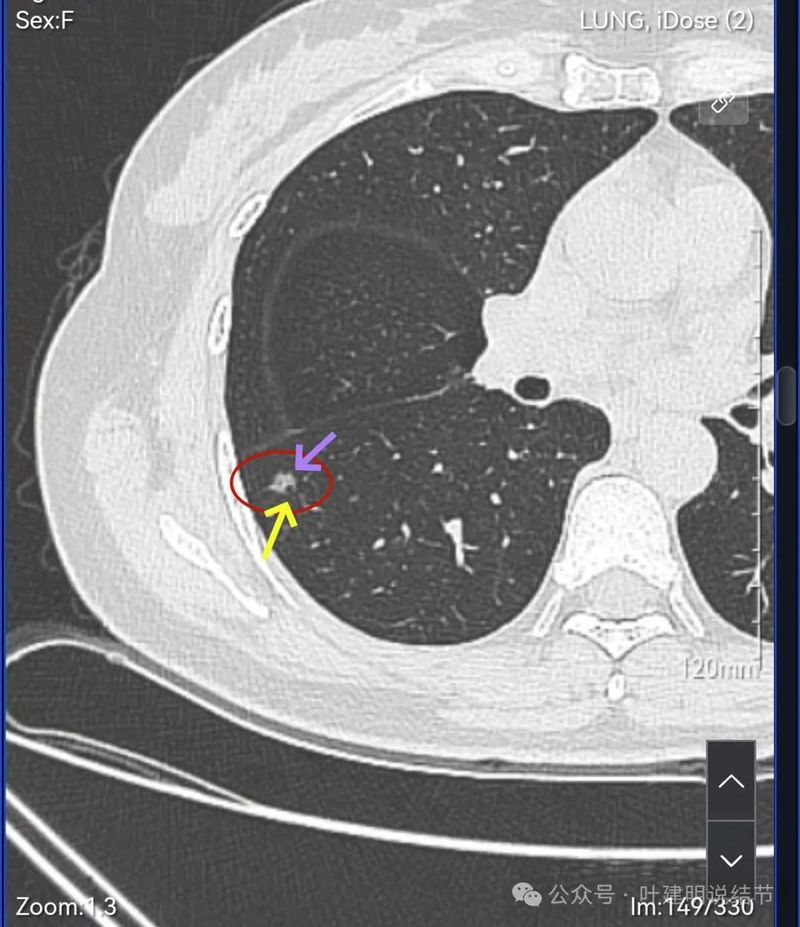

血管进入,表面分叶,密度不均。

密度显杂乱,血管贴边。